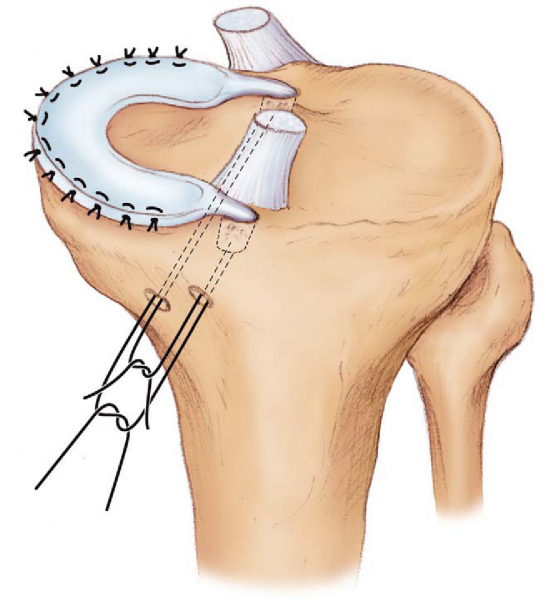

Medial meniscus: A small medial parapatellar arthrotomy is made in line with the medial portal. As for the lateral meniscus insertion, four nonabsorbable sutures are placed within the anterior horn remnant. A small posteromedial incision is then made, centered over the posterior border of the medial collateral ligament. The sartorius fascia is incised, and the interval between the semimembranosus and the medial gastrocnemius is developed, exposing the posteromedial joint capsule. This exposure will be used for inside-out meniscus repair suture techniques.

The posterior horn of the meniscus allograft is delivered through the anteromedial arthrotomy and pulled into the posterior horn tunnel. The posteromedial traction suture is used to reduce the posterior horn into the medial compartment. The posterior bone plug and sutures are pulled into their drill holes by a similar technique, and the allograft is reduced into the medial compartment (

Fig. 50-10

). Once reduction has been achieved, the sutures are tied on the lateral tibial metaphysis over a cortical bridge.

Medial meniscus: The meniscal allograft is secured by arthroscopic inside-out techniques through the posteromedial incision. The anterior horn is secured in a fashion similar to that of the lateral meniscus, and the remaining meniscus is fixed by arthroscopic inside-out techniques. Final fixation of the sutures is performed at 30 degrees of knee flexion after the ACL has been fixed on the tibial side (

Fig. 50-12

).